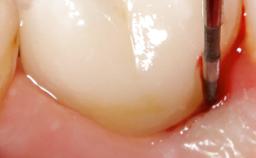

Peri-Implantitis Modified by the Presence of Submucosal Excess Cement: Reconstructive Therapy and a Ten-Year Follow-up

This case outlines the reconstructive therapy by Giovanni Salvi resulting in defect fill and inflammation-free peri-implant soft tissues at 10-year follow up. This case highlights the importance of regular monitoring of implants during supportive therapy.